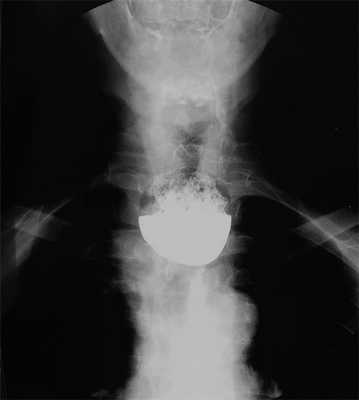

В отделение хирургии (пищевода и желудка) №1 отдела абдоминальной хирургии и онкологии госпитализирован пациент Г., 64 года, с жалобой на затруднение при глотании твердой пищи, срыгивание съеденной пищи в положении лежа, ощущение инородного тела и вздутия на шее после еды, кашель с мокротой, необходимость запивать пищу водой, неприятный запах изо рта. Анамнез заболевания: 7 лет назад стало беспокоить затруднение проглатывания твердой пищи, которое со временем прогрессировало, присоединилось срыгивание съеденной пищи в положении лежа. Явное прогрессирование и ухудшение самочувствия отмечено в течение последних 6 мес. Консультирован в районной поликлинике, назначена ЭГДС. Однако при попытке эзофагоскопии эндоскоп оказывался в слепом кармане, из которого пройти в пищевод технически не удавалось. Выполнена рентгенография пищевода (рис. 1), диагностирован глоточно-пищеводный дивертикул длиной 6 см. МСКТ грудной клетки: диффузный бронхит с признаками бронхиолита слева; по задней стенке пищевода глоточно-пищеводный дивертикул размером 44×29×59 мм с содержимым. В профильных отделениях проведены дополнительное обследование и подготовка к операции по поводу сопутствующих заболеваний: диагностирован хронический аспирационный синдром, хроническая обструктивная болезнь легких, смешанная форма, легкое течение, вне обострения, дыхательная недостаточность, степень 0, хронический мезотимпанит слева вне обострения, смешанная тугоухость III—IV степени слева.

Рис. 1. Рентгенограмма пищевода. Глоточно-пищеводный дивертикул.